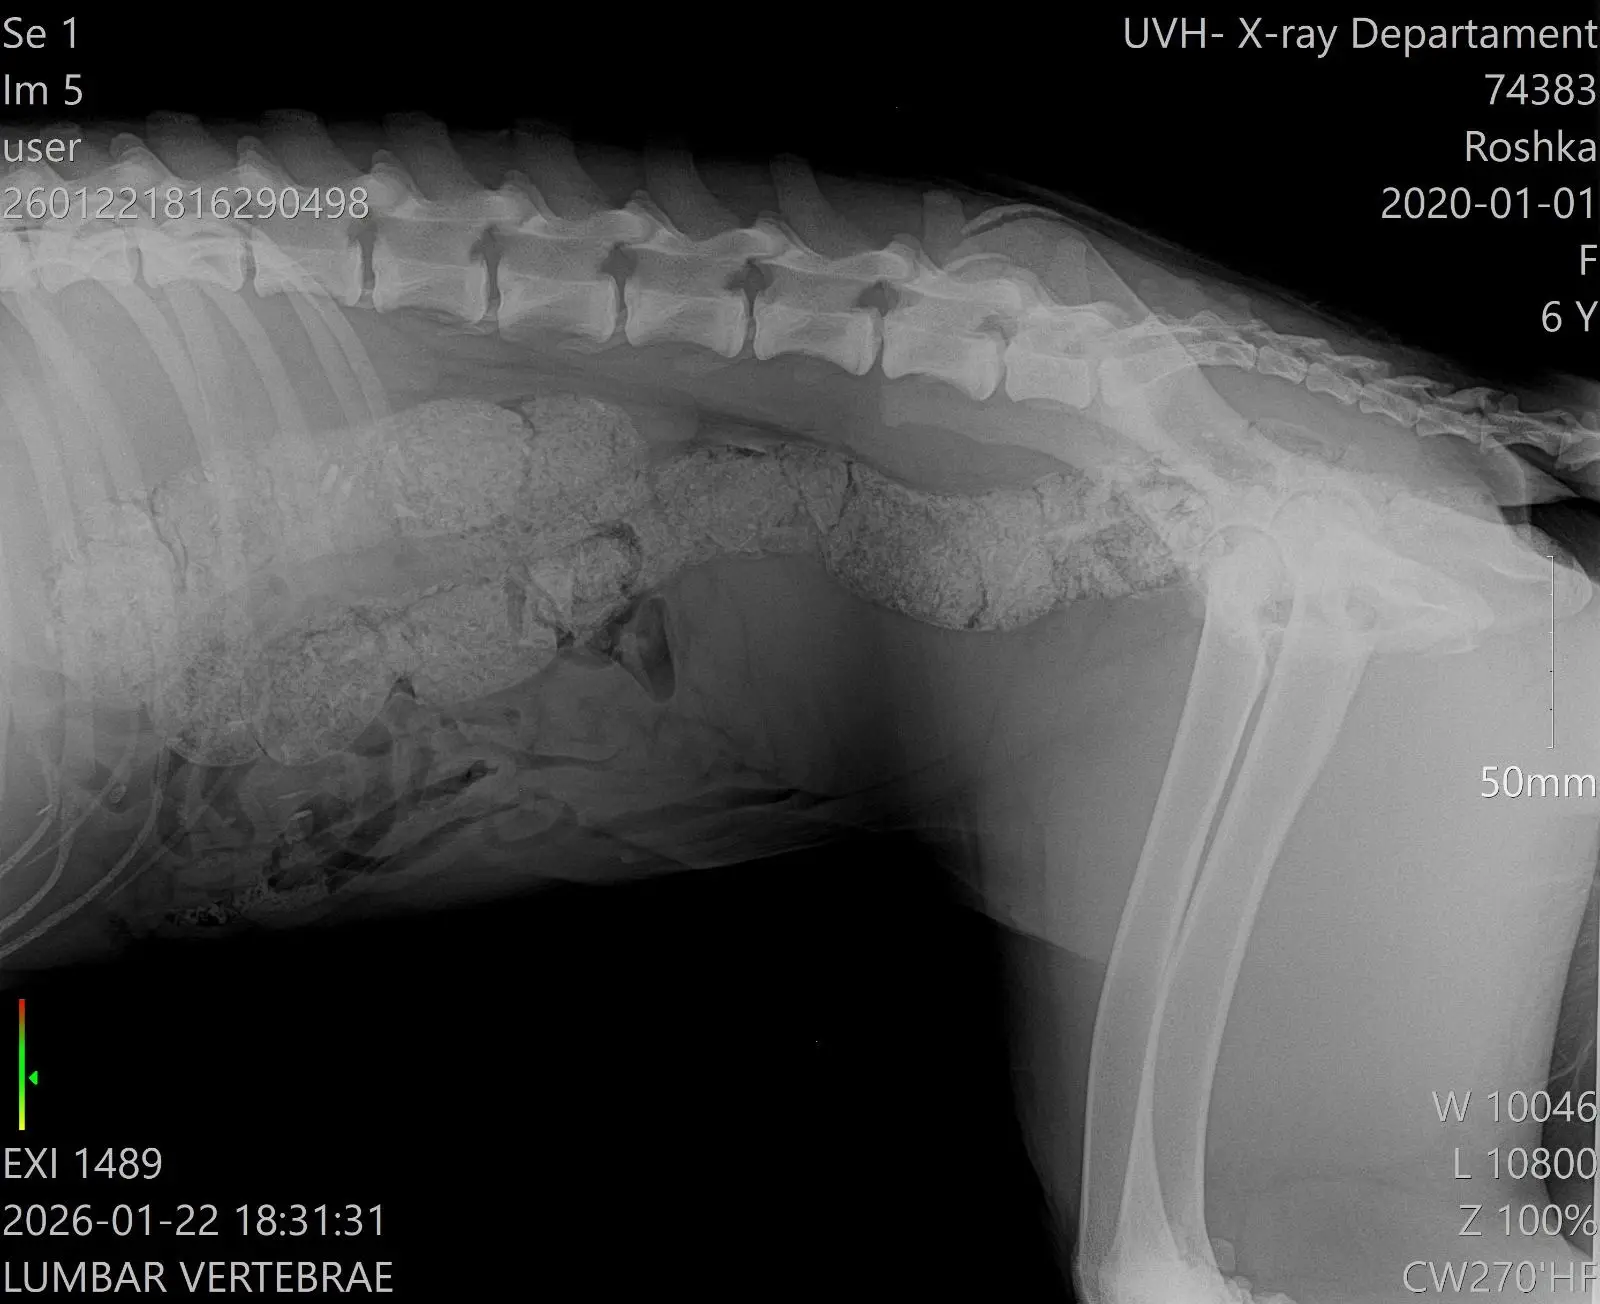

Рошка: 25 кг доброта, която никой не забелязва...Казват, че красотата е в очите на гледащия, но за Рошка очите на хората сякаш остават затворени. Тя не е „мини“ кученце, което можеш да побереш в чанта. Тя е голяма – цели 25 кг – рошава, нетипична и според мнозина... „грозно куче“.

Тъжно е, че малките и пухкави кученца бързо намират помощ, а Рошка, макар и със сърце на великан, не успя да трогне много хора. Тя лежи в клиниката и тихо чака някой да се заинтересува от съдбата ѝ. Не заради външния вид, а заради правото ѝ да живее без болка.

Защо Рошка има нужда от вас

Въпреки силата си, тя не може да се справи сама. Рошка се нуждае от спешни операции на задните краченца. За да може това 25-килограмово тяло да се изправи отново, са необходими импланти и винтове.

Статус: Чака в клиниката за своя шанс.

Тя не е просто „голямо куче“. Тя е душа, която чака своя щастлив край. Вярваме, че нейният човек е някъде там – този, който ще види отвъд рошавата козина и ще оцени волята ѝ за живот.

Всеки лев е стъпка към деня, в който Рошка ще тича свободно